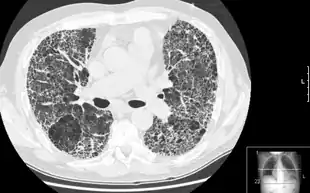

Pulmonary fibrosis is suggested by a history of progressive shortness of breath (dyspnea) with exertion. Sometimes fine inspiratory crackles can be heard at the lung bases on auscultation. A chest X-ray may not be abnormal, but high-resolution CT will often show abnormalities.[3]